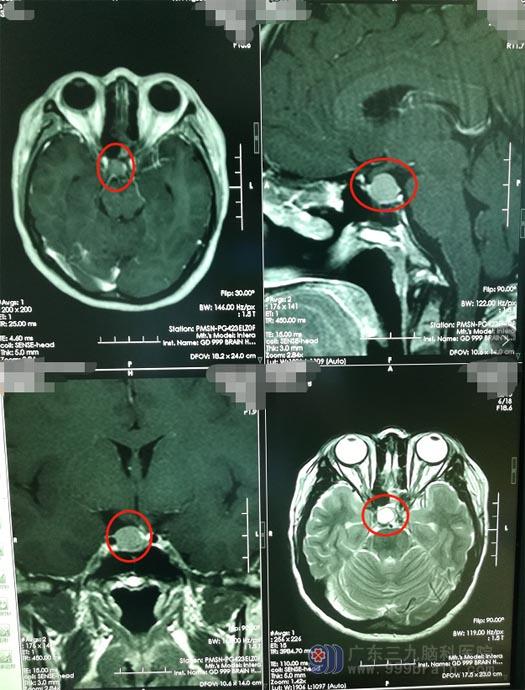

5年前,何女士因为“多尿”在当地医院就诊,头颅MR提示:鞍区垂体瘤,予伽马刀放射治疗。

术后1年,复查头颅MR提示肿瘤较前增大,在全麻下行“经鼻碟鞍区占位切除术”,可效果并不理想。术后2周,何女士在活动时出现严重的脑脊液鼻漏,又一次做了手术补漏。

今年4月初,何女士进行手术后的定期复查,头颅MR检查发现:肿瘤复发。

就在何女士和家人走投无路时,有朋友建议她去广东三九脑科医院试试。接诊的是医院副院长、神经外五科主任鲁明,鲁明仔细查阅了影像资料,结合患者的临床症状,考虑是鞍区垂体瘤术后复发。